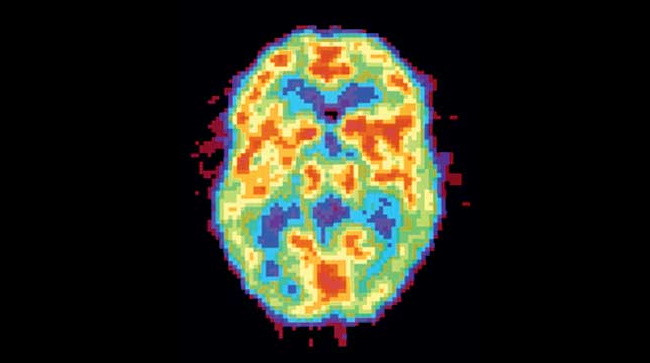

Активность мозга сильно различается не только во время бодрствования и сна — есть множество промежуточных состояний, которые можно различить во время позитронно-эмиссионной томографии.

ДЕПРИВАЦИЯ СНА. Активность мозга очень долго не спавшего человека снижена и похожа на стадию глубокого сна